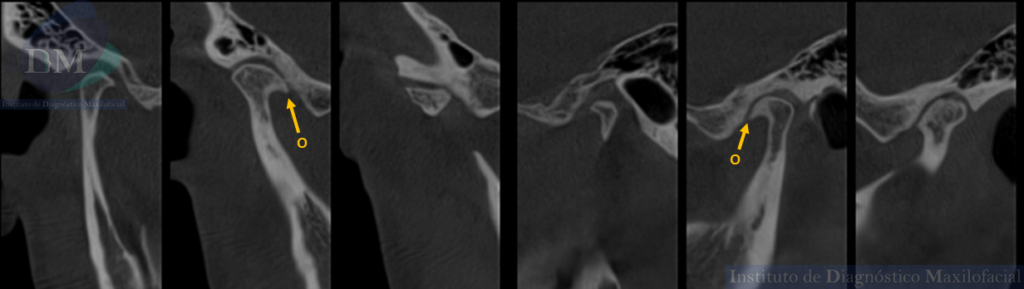

A la ampliación de estudio con tomografía computarizada de haz cónico (TCHC) se revelan hallazgos adicionales como:

- Osteofitos (O), indicativos de crecimiento óseo anómalo en los cóndilos mandibulares.

- Reducción de los espacios interarticulares en ambas articulaciones temporomandibulares, sugiriendo un estrechamiento del espacio articular.

CORTES SAGITALES